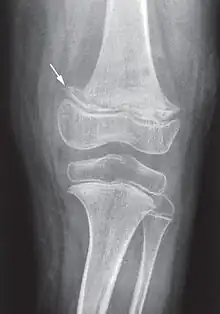

X-ray of the knee joint (arrow indicates scurvy line)

While many animals produce their own vitamin C, humans and a few others do not.[2] Vitamin C is an antioxidant, is required to make the building blocks for collagen, carnitine, and catecholamines, and assists the intestines in the absorption of iron from foods.[2][4][5] Diagnosis is typically based on outward appearance, X-rays, and improvement after treatment.[2]

Diagnosis is typically based on physical signs, X-rays, and improvement after treatment.[2]